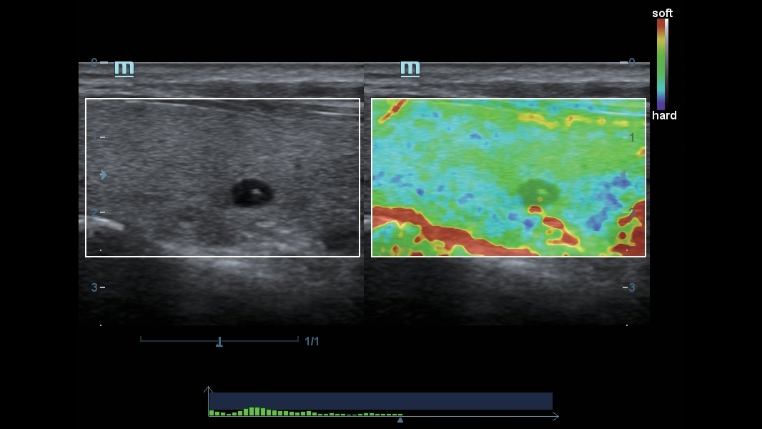

Klasyczne technologie obrazowania: zwi?kszenie jako?ci w diagnostyce

Poprzez zastosowanie klasycznych technologii obrazowania, wykorzystywanych w uznanych systemach ultrasonograficznych, DC-40 Full HD dostarcza doskonale szczeg├│?owy obraz.

- iClear (technologia redukcji zak?óceń obrazowania)

- PSH (obrazowanie harmoniczne z odwr├│ceniem fazy)

- iBeam (technologia obrazowania z wykorzystaniem skrzy?owanych ultrad?wi?k├│w)